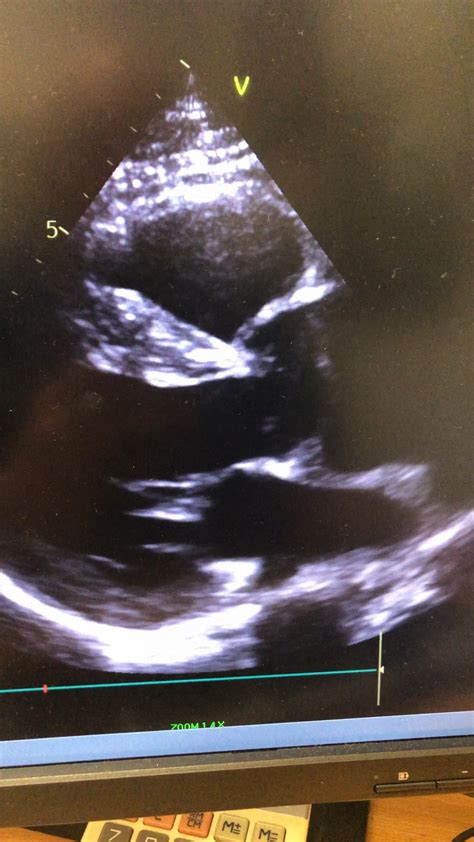

If you have recently visited a cardiologist or received a referral for a diagnostic heart test, you might be wondering, what is a TTE? A Transthoracic Echocardiogram (TTE) is one of the most common, non-invasive, and highly effective imaging tests used in modern medicine to evaluate the structure and function of the heart. By utilizing ultrasound technology—the same type of technology used to look at a developing fetus during pregnancy—a TTE allows healthcare professionals to visualize your heart in real-time without making any incisions.

At its core, a Transthoracic Echocardiogram (TTE) is a painless diagnostic procedure that captures images of the heart using sound waves. The term "transthoracic" simply means "through the chest," indicating that the probe (transducer) is placed on the surface of your chest wall to obtain the images. It provides a detailed view of the heart's chambers, valves, and walls, helping doctors assess how well the organ is pumping blood throughout the body.

4. Imaging: The sonographer moves the transducer firmly around your chest, applying slight pressure to obtain different angles of the heart. You may hear whooshing sounds—these are the Doppler signals used to measure the speed and direction of blood flow.